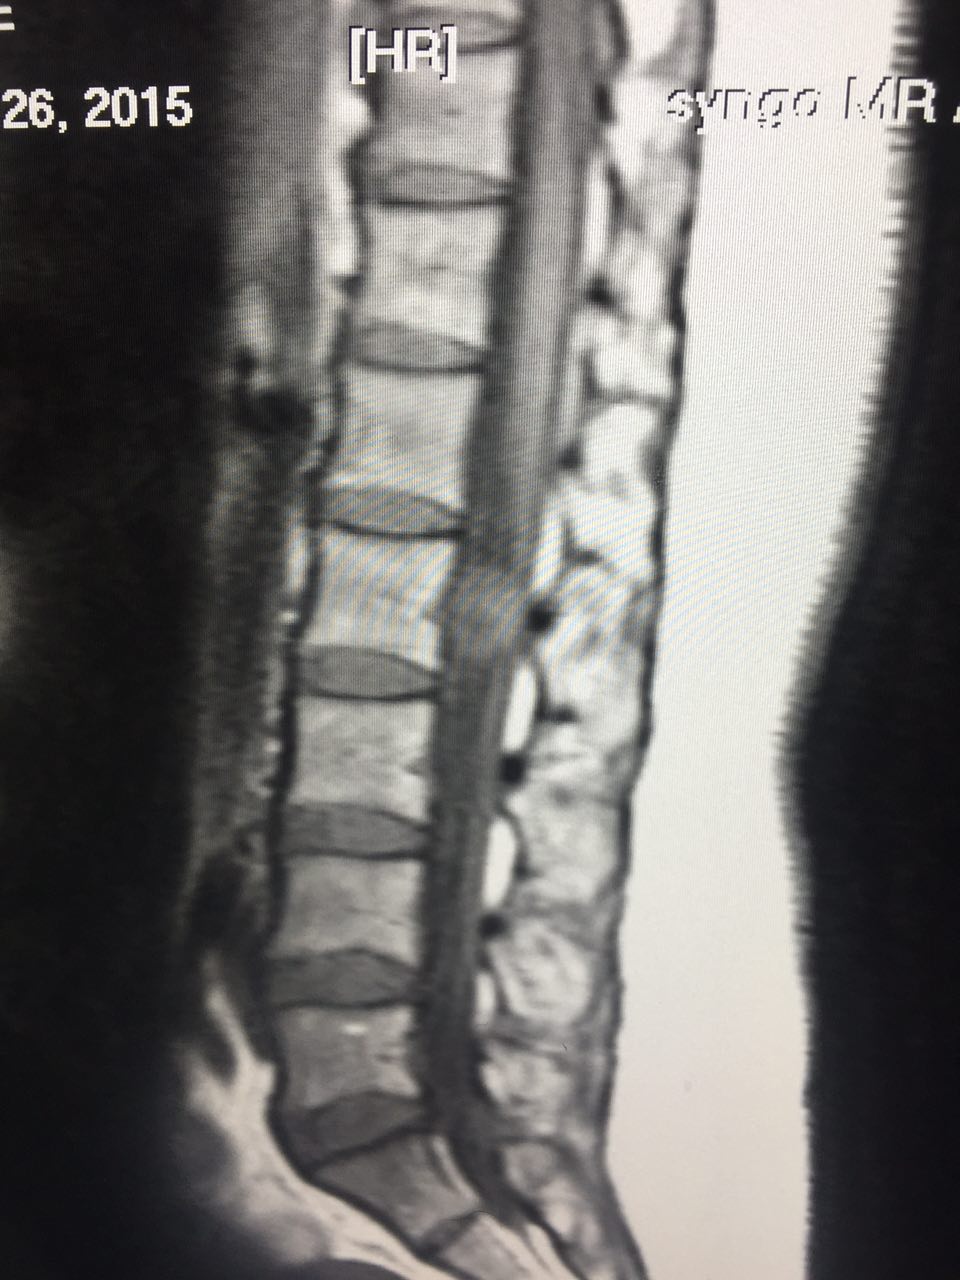

Spine- intradural and extra medullary tumor (5)